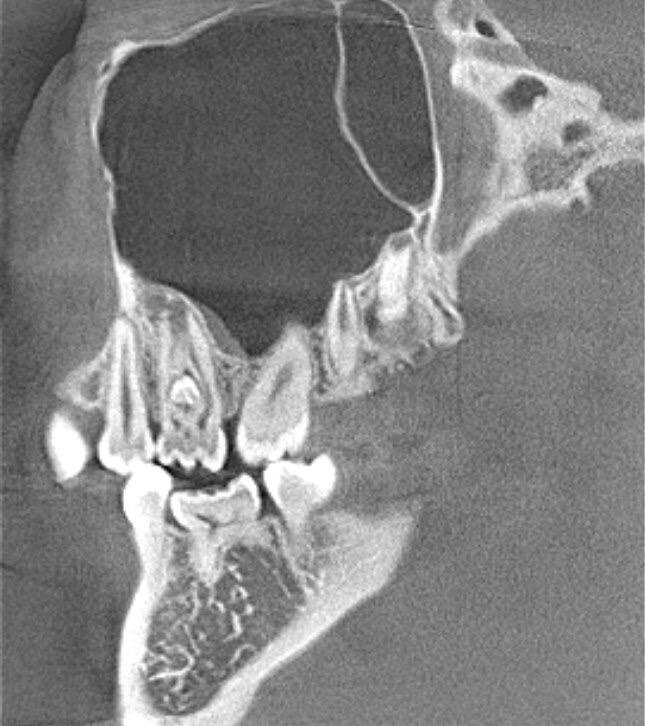

Вы слышали когда нибудь про "беременные зубы" ? А они реально существуют 😅 Называется такой дефект развития ❗️dens invaginatus ❗️или зуб в зубе. Такое происходит из за того, что коронковая часть зачатка зуба еще до того, как он прошел кальцификацию, совершает инвагинационное выпячивание внутрь самой себя. Впервые вышеозначенная аномалия была выявлена в 1794 году в зубах китов, у человека же подобный диагноз дебютировал в 1856 году. Встречаемость в популяции, по данным различных исследователей, от 0,5 до 13%. Боковые резцы верхней челюсти — 5%; Центральные резцы верхней челюсти — 8%; Премоляры нижней челюсти — 6%; Мезиоденс (сверхкомплектный зуб между центральными резцами) — 9%; Клыки верхней и нижней челюсти — 6%. На самом деле встречается очень и очень редко, и поговорив со своими коллегами, многие из них про это только в учебниках читали🎓 Но мне посчастливилось встретиться с таким диагнозом уже второй раз😎 Как правило пациент не подозревает об этом и это случайная находка на КЛКТ

Такое происходит из за того, что коронковая часть зачатка зуба еще до того, как он прошел кальцификацию, совершает инвагинационное выпячивание внутрь самой себя.

Как правило пациент не подозревает об этом и это случайная находка на КЛКТ, либо обращается с болью...

А дальше в зависимости от локализации такой "находки" выбирается подходящий план лечения!